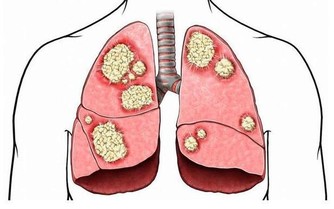

圖片來源:衛生福利部粉專2020-02月武漢肺炎(新型冠狀病毒肺炎)疫情擴大,加上最近的寒流冷颼颼,讓病毒存活率又更高了~為了自己跟他人的健康安全著想,想要有效防止武漢病毒大擴散,養成「戴口罩」的習慣真的好重要,口罩不離口鼻,並要勤洗手,這兩點最為關鍵!!

市面上常見的口罩大概分為以下幾種:外科手術口罩、N95口罩、棉布口罩、海綿口罩等。其中常見的綠色口罩是醫療級的外科口罩,三層設計能有效阻隔細菌與病毒,避免我們透過口鼻將細菌吸入體內。N95口罩能有效阻隔空氣傳播的病菌病毒,缺點是透氣度低,不適合常戴,而政府也表示,現階段的防疫無需配戴N95口罩。其餘像是常見的可洗式棉布口罩或是活性碳口罩等,只能阻隔大型灰塵及異物,或是花粉、塵埃、霧霾,此時都無法阻隔經由口沫傳染的新型冠狀病毒。